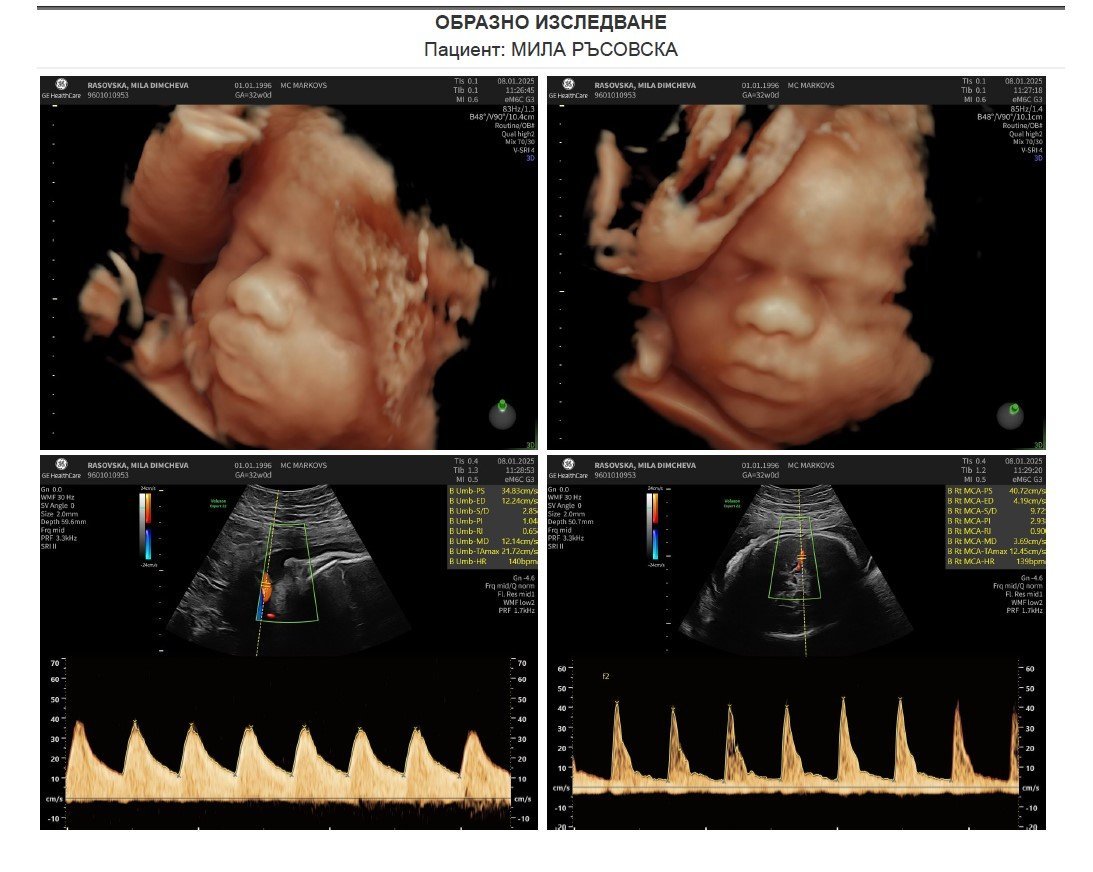

Днес съм на 3та фетална и очаквам бебетата да ги видим с нетърпение в Клиника Марковс и да ни кажат, че всичко е окей с тях и са наддали въпреки, моите връщания на поръчката постоянно.

И аз се включвам да споделя как мина 3тата фетална при Проф.Марков. Бебетата вървят по 2кила горе долу всяко. Каза че си отговаряли по кг на 32г.с, в която съм и днес. Но за близнаци били едри и големи бебета и всяко ще излезе накрая с по 3кила, така че ми препоръча секцио. Но понеже са разположени главично и двете вече и нямат опция да се обърнат никаква, ще реша с моя АГ как ще процедираме - искам естествено раждане като цяло и ако няма усложнения. Главите им са вече 9.2 и 9.8см, което каза, че за естествено раждане почти няма как да се говори с тези големи размери на главите. Препоръчително е за да нямало усложнения да ги вадим в 36 или 37г.с, което ще рече, че февруари месец излизат, мърдане няма. Шийката ми е 3 и нещо, запазена отвсякъде и ако тя издържи до тези гестационни седмици, ще е добре, но ако тя поддаде бебе 1, което е вече на шийката ми с главата и я бута, директно ще тръгне да излиза по-рано. Каза също така,че за близнаци вървят доста големи бебетата и то не поради причината, че съм като кг много, а че и двамата сме високи и едри по 1,70 и 1,90 родители. Пулсовете им са по 140bpm.